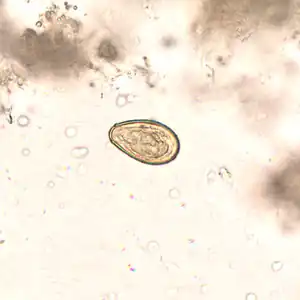

The medical diagnosis is established by finding eggs of Opisthorchis viverrini in feces[3] using the Kato technique.[10] An antigen 89 kDa of Opisthorchis viverrini can be detected by ELISA test.[3]

Egg O. viverrini in unstained wet mount of concentrated stool[2] -